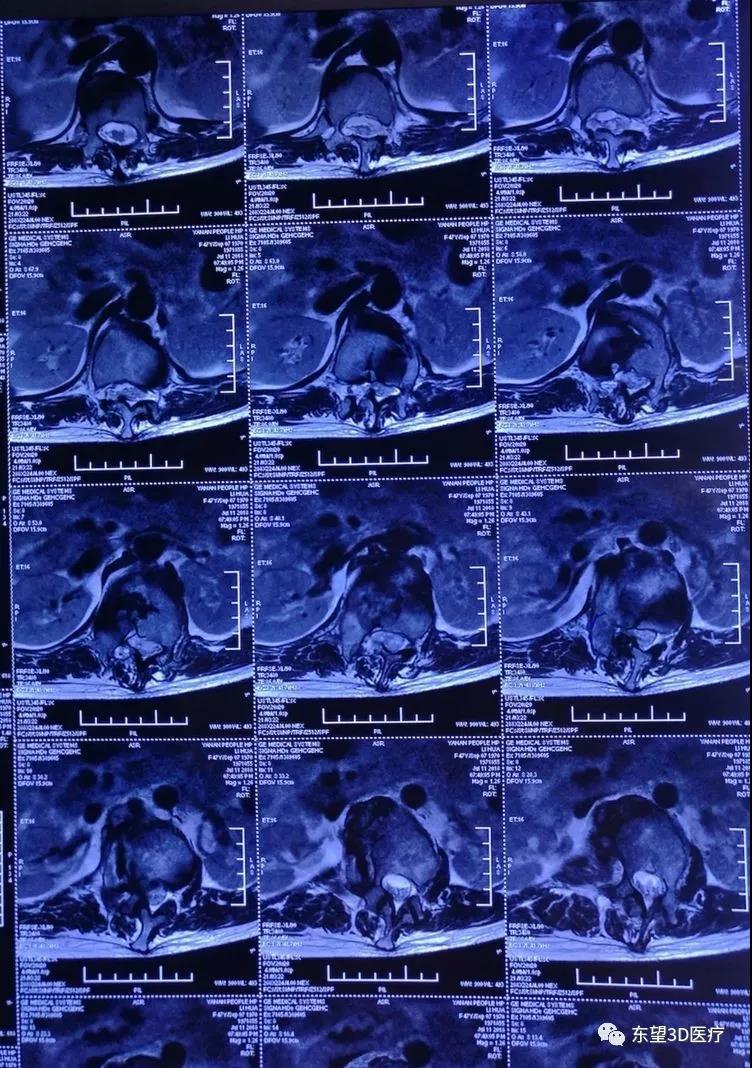

術前MRI檢查,硬膜囊脊髓明顯受壓

\